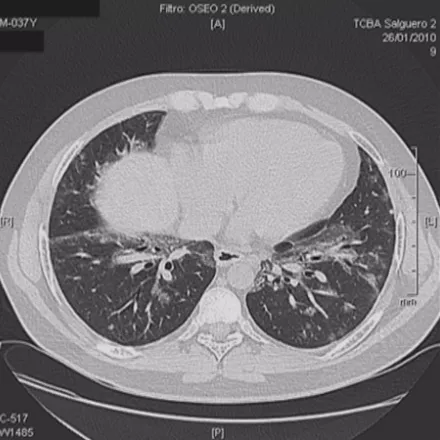

多灶性COP

多灶性机化性肺炎也可以表现为胸膜下或支气管周围的磨玻璃密度片影伴实变,支气管或细支气管周围边界不清的磨玻璃密度小结节,大的结节和肿块,反Halo征。因此,大家在做肺结节鉴别诊断的时候一定要考虑到该疾病。

BOOP

双肺多发的磨玻璃影或斑片实变影,沿支气管血管束分布或位于胸膜下,在一个或多个结节内可见到支气管充气征,有时可见反晕征。临床上要是碰到多发性肺结节超过五个的问题倒不大,要是只有两、三个还是需要警惕的。